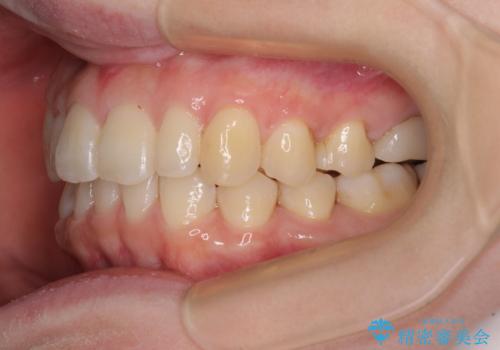

先天欠損のある歯列 インビザライン矯正

- 上顎前歯の突出感を気にして来院された患者様です。

下顎前歯2本が先天欠損しており、上顎歯列に対して、下顎歯列がアンバランスに小さい状況でした。

左右上顎側切歯2本が矮小歯であるため、上顎の抜歯ではなく、IPR(歯と歯の間を削る)と歯列全体の後方移動によってバランスを整えることとしました。

目立ちにくい装置を希望されたため、インビザラインにて治療を行うこととしました。

歯列のバランスが悪く、インビザライン矯正特有の奥歯の噛みにくさがなかなか改善されず、治療期間が長期化してしまいました。